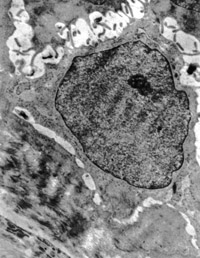

5-2-14 愈后新生皮肤真皮内纤维细胞呈常态,胶原纤维粗细均匀,排列有序,达生理性愈合 TEM×10000